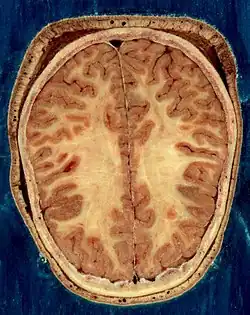

The vertebrate nervous system can also be divided into areas called gray matter and white matter.[19] Gray matter (which is only gray in preserved tissue, and is better described as pink or light brown in living tissue) contains a high proportion of cell bodies of neurons. White matter is composed mainly of myelinated axons, and takes its color from the myelin. White matter includes all of the nerves, and much of the interior of the brain and spinal cord. Gray matter is found in clusters of neurons in the brain and spinal cord, and in cortical layers that line their surfaces. There is an anatomical convention that a cluster of neurons in the brain or spinal cord is called a nucleus, whereas a cluster of neurons in the periphery is called a ganglion.[20] There are, however, a few exceptions to this rule, notably including the part of the forebrain called the basal ganglia.[21]